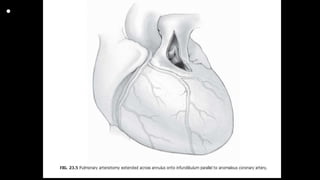

outflow tract. The parietal

band is transected to enlarge